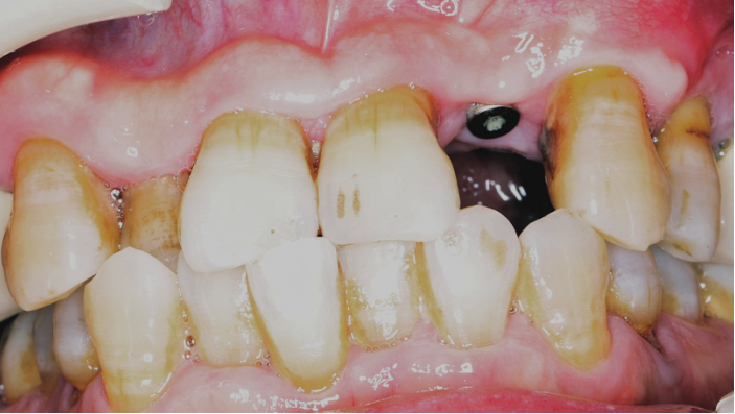

术后5个月完成修复

常规印模制取,应患者要求,术后5个月完成修复。

戴牙后20天复查X线检查

术前术后对比

由于患者需求因素未进行“即刻临时修复体”的制作和个性化过度义齿试戴,一定程度上影响了术后美学效果的提升。

修复阶段,使用个性化印模制备模型,订制个性化基台螺丝固位,改变了患牙原始的反合情况,尽量纠正为浅覆盖,美观方面有所提升。